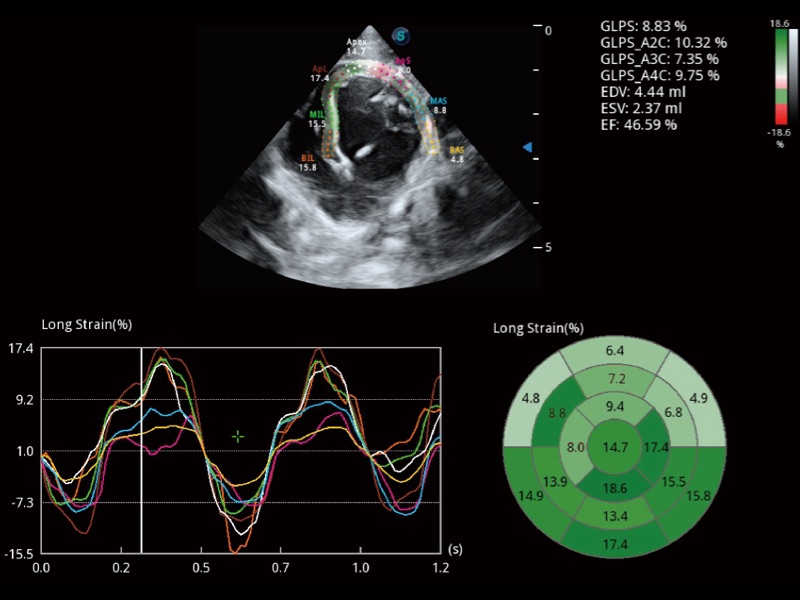

能夠基于左心室壁追蹤和辛普森法,自動(dòng)計(jì)算射血分?jǐn)?shù),支持多個(gè)可移動(dòng)點(diǎn)描跡,與手動(dòng)測(cè)量相比,極大節(jié)省了動(dòng)物醫(yī)生的時(shí)間和精力。

具備多種協(xié)議可選,同時(shí)支持17階段劃分法和專業(yè)的SE報(bào)告。

通過(guò)360度任意調(diào)節(jié)3條M型取樣線,在同一心動(dòng)周期上觀察心臟不同位置的運(yùn)動(dòng)曲線,得到準(zhǔn)確的心功能測(cè)量數(shù)據(jù),有效評(píng)估心肌運(yùn)動(dòng)及左心室功能。

實(shí)時(shí)用顏色表示心肌組織運(yùn)動(dòng),觀察和定量組織的運(yùn)動(dòng)情況,對(duì)快速檢測(cè)與評(píng)估心肌的灌注和活性、電傳導(dǎo)及心肌收縮和舒張功能等均能提供重要的診斷信息。